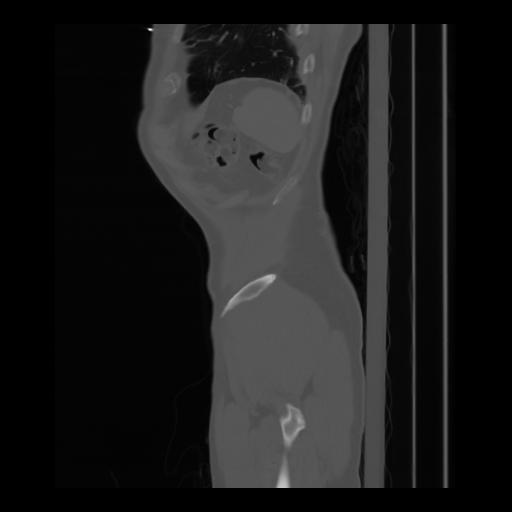

36 CUERPO,CE,Sagittal,3.000,CUERPO,Sagittal,